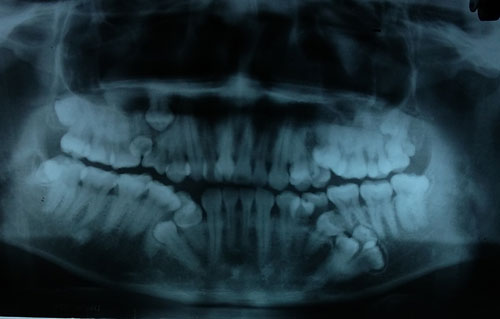

Bác sĩ khám răng cho một bệnh nhân. Bác sĩ tí thì ngất vì hàm răng của chàng thanh niên này. Làm gì chẳng đau khi hàm mọc thừa 13 chiếc và 4 chiến đang chiến để không thua kém chiêc khác.

Trong tuần này, các bác sĩ Bệnh viện Việt Nam - Cu Ba (Hà Nội) sẽ phẫu thuật tạo hình loại bỏ răng thừa cho bệnh nhân. Anh Văn Sơn 28 tuổi, cho biết từ năm học lớp 10 cứ mỗi năm lại thấy mọc thêm một chiếc răng, lúc hàm trên khi hàm dưới. Nghĩ là răng mọc lẫy, không thấy khó chịu hay vướng víu gì nên anh không đi khám răng. Lần khám gần đây nhất đã lâu, anh chỉ hàn răng bị sâu. Khi đó anh mới mọc 4 răng thừa, bác sĩ không tư vấn gì. Cách đây 10 ngày, đau nhức răng ở hàm trên bên trái không chịu được, anh Sơn đến Bệnh viện Việt Nam - Cu Ba khám. Bác sĩ bất ngờ khi phát hiện ngoài bị răng sâu, bệnh nhân còn mọc thừa đến 13 chiếc răng.

Bác sĩ Nguyễn Thị Thanh Châm, khoa Phẫu thuật Tạo hình Hàm mặt, Bệnh viện Việt Nam - Cu Ba cho biết, bệnh nhân mọc thừa đến 13 chiếc răng số 4 và 5 trên hai hàm - răng hàm nhỏ. Các răng mọc lệch, chen chúc, khó vệ sinh, cặn thức ăn dính vào kẽ lâu ngày tạo thành các mảng bám, một răng bị sâu viêm tủy khiến bệnh nhân đau nhức khó chịu.

Bác sĩ Nguyễn Thanh Thái, Trưởng khoa Phẫu thuật Tạo hình Hàm mặt, cho biết thêm, ngoài 13 răng đã mọc thừa, kết quả chụp CT hàm dưới còn phát hiện thêm 4 mầm răng. Những răng này chưa mọc nên sẽ được theo dõi và xử lý sau.

Hàm dưới bệnh nhân còn 4 mầm răng chưa nhô lên. Ảnh: BSCC.